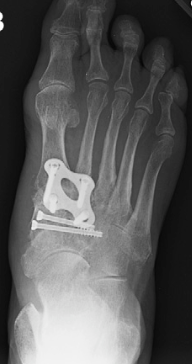

Midfoot arthrodesis is performed to treat painful midfoot arthritis, instability, or deformity, often following trauma such as a Lisfranc injury. The procedure stabilizes the midfoot by fusing the affected joints.

Midfoot arthrodesis involves removing remaining cartilage from the affected midfoot joints and securing them in proper alignment using internal fixation. The specific joints fused depend on the location and extent of disease.